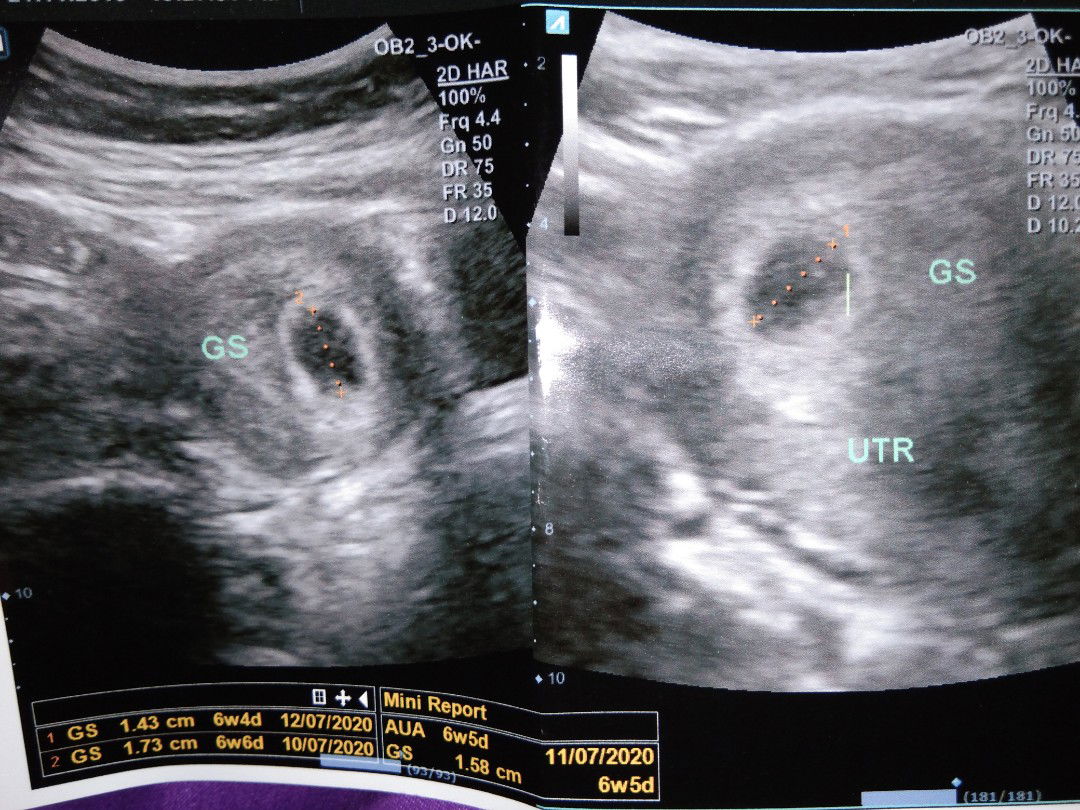

6w

Pagi bunda² ,smlm aku usg kandungan aku usia 6w alhamdulillah, tpi blm kliatan janin nya baru kantung nya kira² brp minggu bisa kliatan ya bunda ini ank pertma jd masi blm paham ?